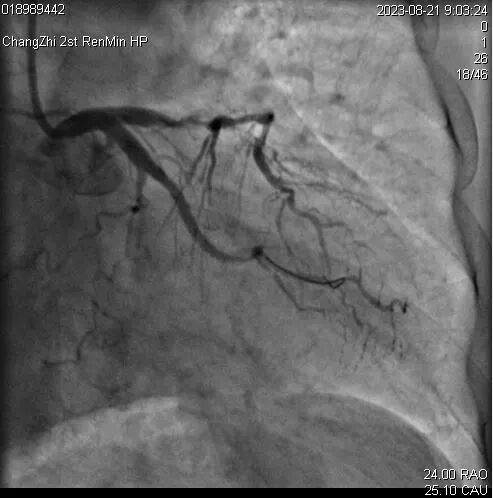

患者王某,女,58岁,既往高血压病史30年。糖尿病病史18年。脑梗死病史18年,言语迟钝。患者近10月反复心前区不适,2023年8月就诊于长治二院心血管内科,完善冠状动脉造影提示三支病变:前降支近中段弥漫性狭窄80-95%,回旋支远段闭塞,钝缘支近段闭塞。右冠近段弥漫性狭窄85-90%,后三叉开口前闭塞。

8月份支架植入术后造影

2023年10月首都医科大学附属安贞医院孙涛主任医师为其实施手术,结合患者前降支血管严重迂曲,钙化严重,首先对患者进行了血管内超声提示冠脉内270°-360°狭窄。考虑患者血管病变严重,球囊扩张及支架植入手术风险极高,充分考虑后对患者行冠状动脉震波球囊处理,后对血管再次行血管内超声提示冠脉内环形钙化全部被震裂,术中顺利开通前降支并植入支架2枚。患者症状明显好转后出院。